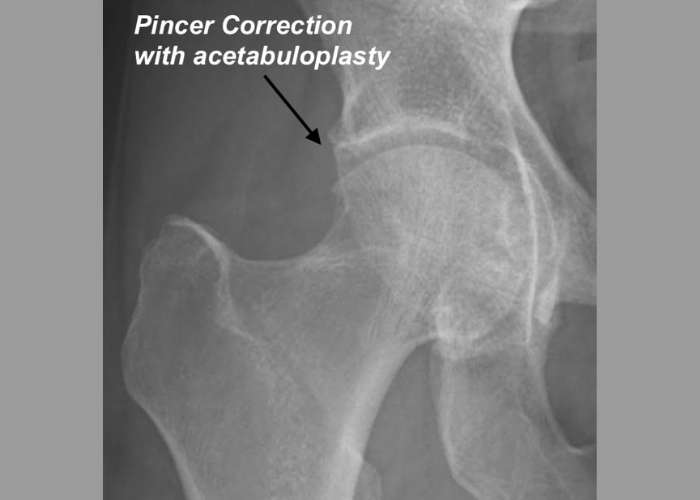

Surgical treatment for pincer hip impingement:

If the painful symptoms are not resolved by non-surgical methods surgery may become necessary. Depending on the exact diagnosis, Dr. Patel may perform one or more of the following surgical procedures: